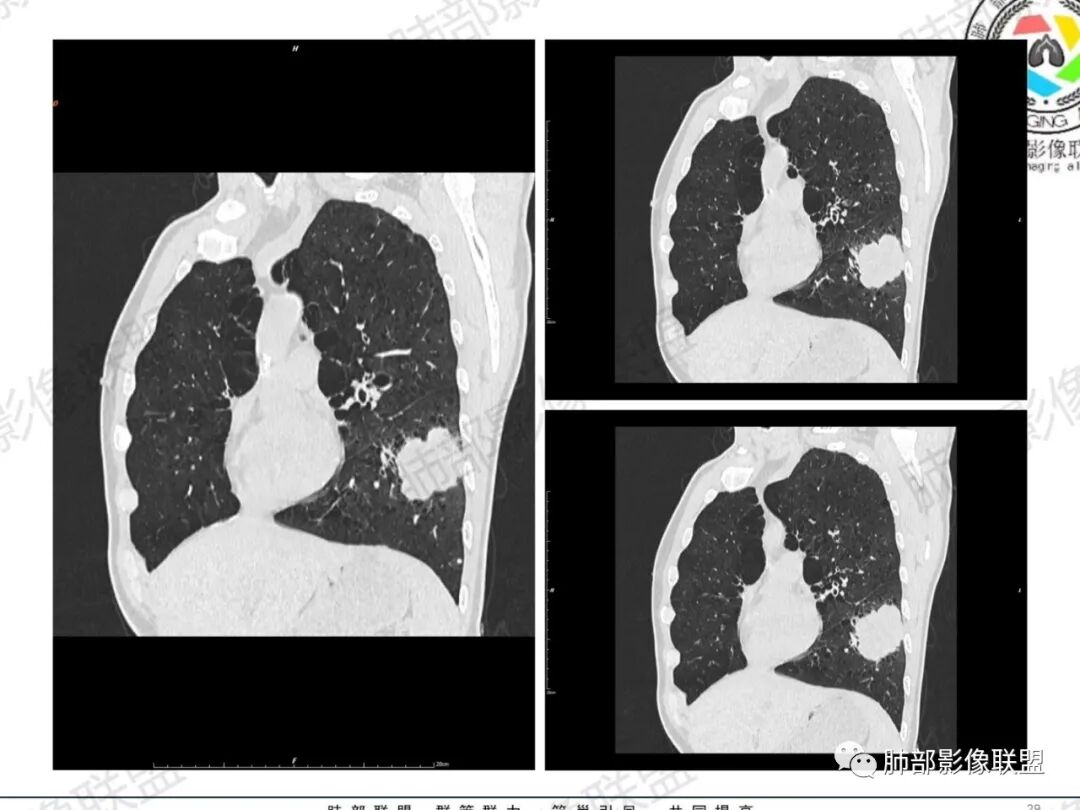

一切∮随缘:左肺下叶不规则肿块,边缘光滑,平直,局部彭隆,分叶,近端支气管堵塞,远端与胸膜相贴,平扫密度尚均匀,增强后不均匀强化,内部可见低密度坏死,胸膜下多发肺气肿,伴双肺散在光滑小结节,实验室肿瘤标志物高,考虑恶性:神经内分泌癌(大细胞),腺癌,鳞癌。

琦遇:恶性没有问题,肺气肿底子、病灶分叶、少许毛刺、叶间胸膜凹陷、部分边缘可见清晰的GGO、胸膜牵拉凹陷、局部胸水、近端支气管截断、部分支气管被推移、占位效应明显、强化特点为不均匀强化、内部有少许沼泽样低强化区,强化部分轻中强化为主、余肺可见转移性结节、左肺上叶似为囊腔型腺癌一枚,肿瘤标志物提示非小、神经内分泌,综合分析考虑大神泌、腺癌、腺鳞癌、鳞癌  同时左肺上叶囊腔型腺癌  肺转移

飞鹰行动:中年人,男性,胸疼入院,左肺下叶占位,张力较高,边界可见分叶,局部可见明显收缩性改变,增强病灶内部有延迟强化表现,考虑恶性病变,大细胞癌伴肺内转移或者囊腔样腺癌伴转移。

蕊:中老年男性,吸烟史,肺气肿背景,左肺上叶类圆形肿块影,边界清晰,边缘凹凸不平,有分叶,支气管进入阻断,临近胸膜栽赃,整体病灶膨隆,局部周围可以清晰ggo,临近叶间裂内凹,轻度强化,并可见多个低密度区,坏死可能,界线不清;肺内多结节,边缘光滑,考虑恶性伴转移,鳞癌、腺癌

傅昌瑜:中老年男性,肺气肿背景,右胸背疼痛1周。CEA、NSE、CYFRA—211升高。左上肺混合磨玻璃结节,内见较多空泡和扩张支气管。左下肺胸膜下肿块,边缘较光滑,深分叶,似有血管进入,与支气管关系不清,内见不均匀强化,见沼泽地样坏死,有胸膜栽赃。另两肺多发圆形小结节。考虑恶性并肺内转移,多原发可能性大,左上肺腺癌,左下肺病理难以判断,小细胞癌?鳞癌?

小锁:中老年男性,肺气肿背景,右胸背疼痛1周。CEA、NSE、CYFRA—211升高。左上肺混合磨玻璃结节,边界清楚,内见较多空泡。左下肺肿块,边缘清楚,深分叶,有血管和支气管进入,胸膜凹陷。另两肺多发圆形小结节。考虑双发原位癌,左上肺腺癌,左下肺大神泌或腺鳞癌可能,肺内转移。

蓝天白云:中年男性,肺气肿背景,左肺下叶肿块,边缘膨隆,有分叶,内有湖泊样坏死,有轻中度强化,局部胸膜栽赃,收缩力不强,周围见肺气肿征象。左肺上叶混合磨玻璃影,边界清楚,考虑都是恶性,左上肺iac,左下肺腺鳞癌,或大细胞肺癌可能。两肺多发结节,考虑转移

毛勤香:老年男性,肺气肿背景,左肺下叶肿块,分叶,边缘光滑,土豆块样,细支气管闭塞,增强轻度不均匀强化,似有坏死,左肺另见多发结节,淋巴结未见明显肿大,恶性确定,吸烟史,鳞癌破坏力强,侵袭力差,多原发的一般很少多于3个,故排后,首先考虑神经内分泌癌,局部血管穿行,鉴别淋巴瘤

周太狼:中年男性,吸烟、高血压史,肿瘤指标升高,肺气肿背景下,左肺下叶肿块影,分叶、膨隆、未跨叶裂,支气管截断,不均匀强化。另双肺多发结节及磨玻璃影,左肺上叶混合磨玻璃,内可见多发空泡影。整体考虑恶性,肺癌伴肺内转移,左下肺鳞癌?神经内分泌癌?左肺上叶囊腔腺癌?